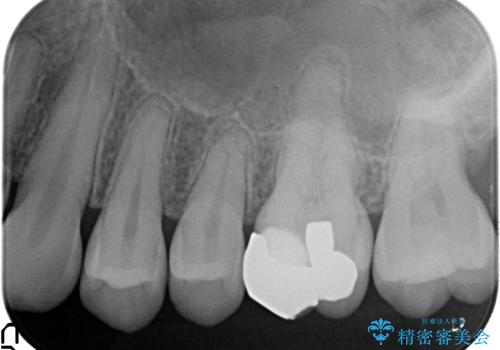

- ものを咬むと左上の奥歯が痛むので診て欲しいといらっしゃった方の症例です。

診査の結果、左上6が失活(歯の神経が死んでいる状態)しており根尖病変を認めたため、根管治療を行いました。

根尖病変の縮小及び症状の消失を確認後、オールセラミッククラウンによる補綴を行いました。